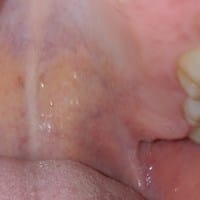

¿Caseum amigdalar o se trata de una infección?